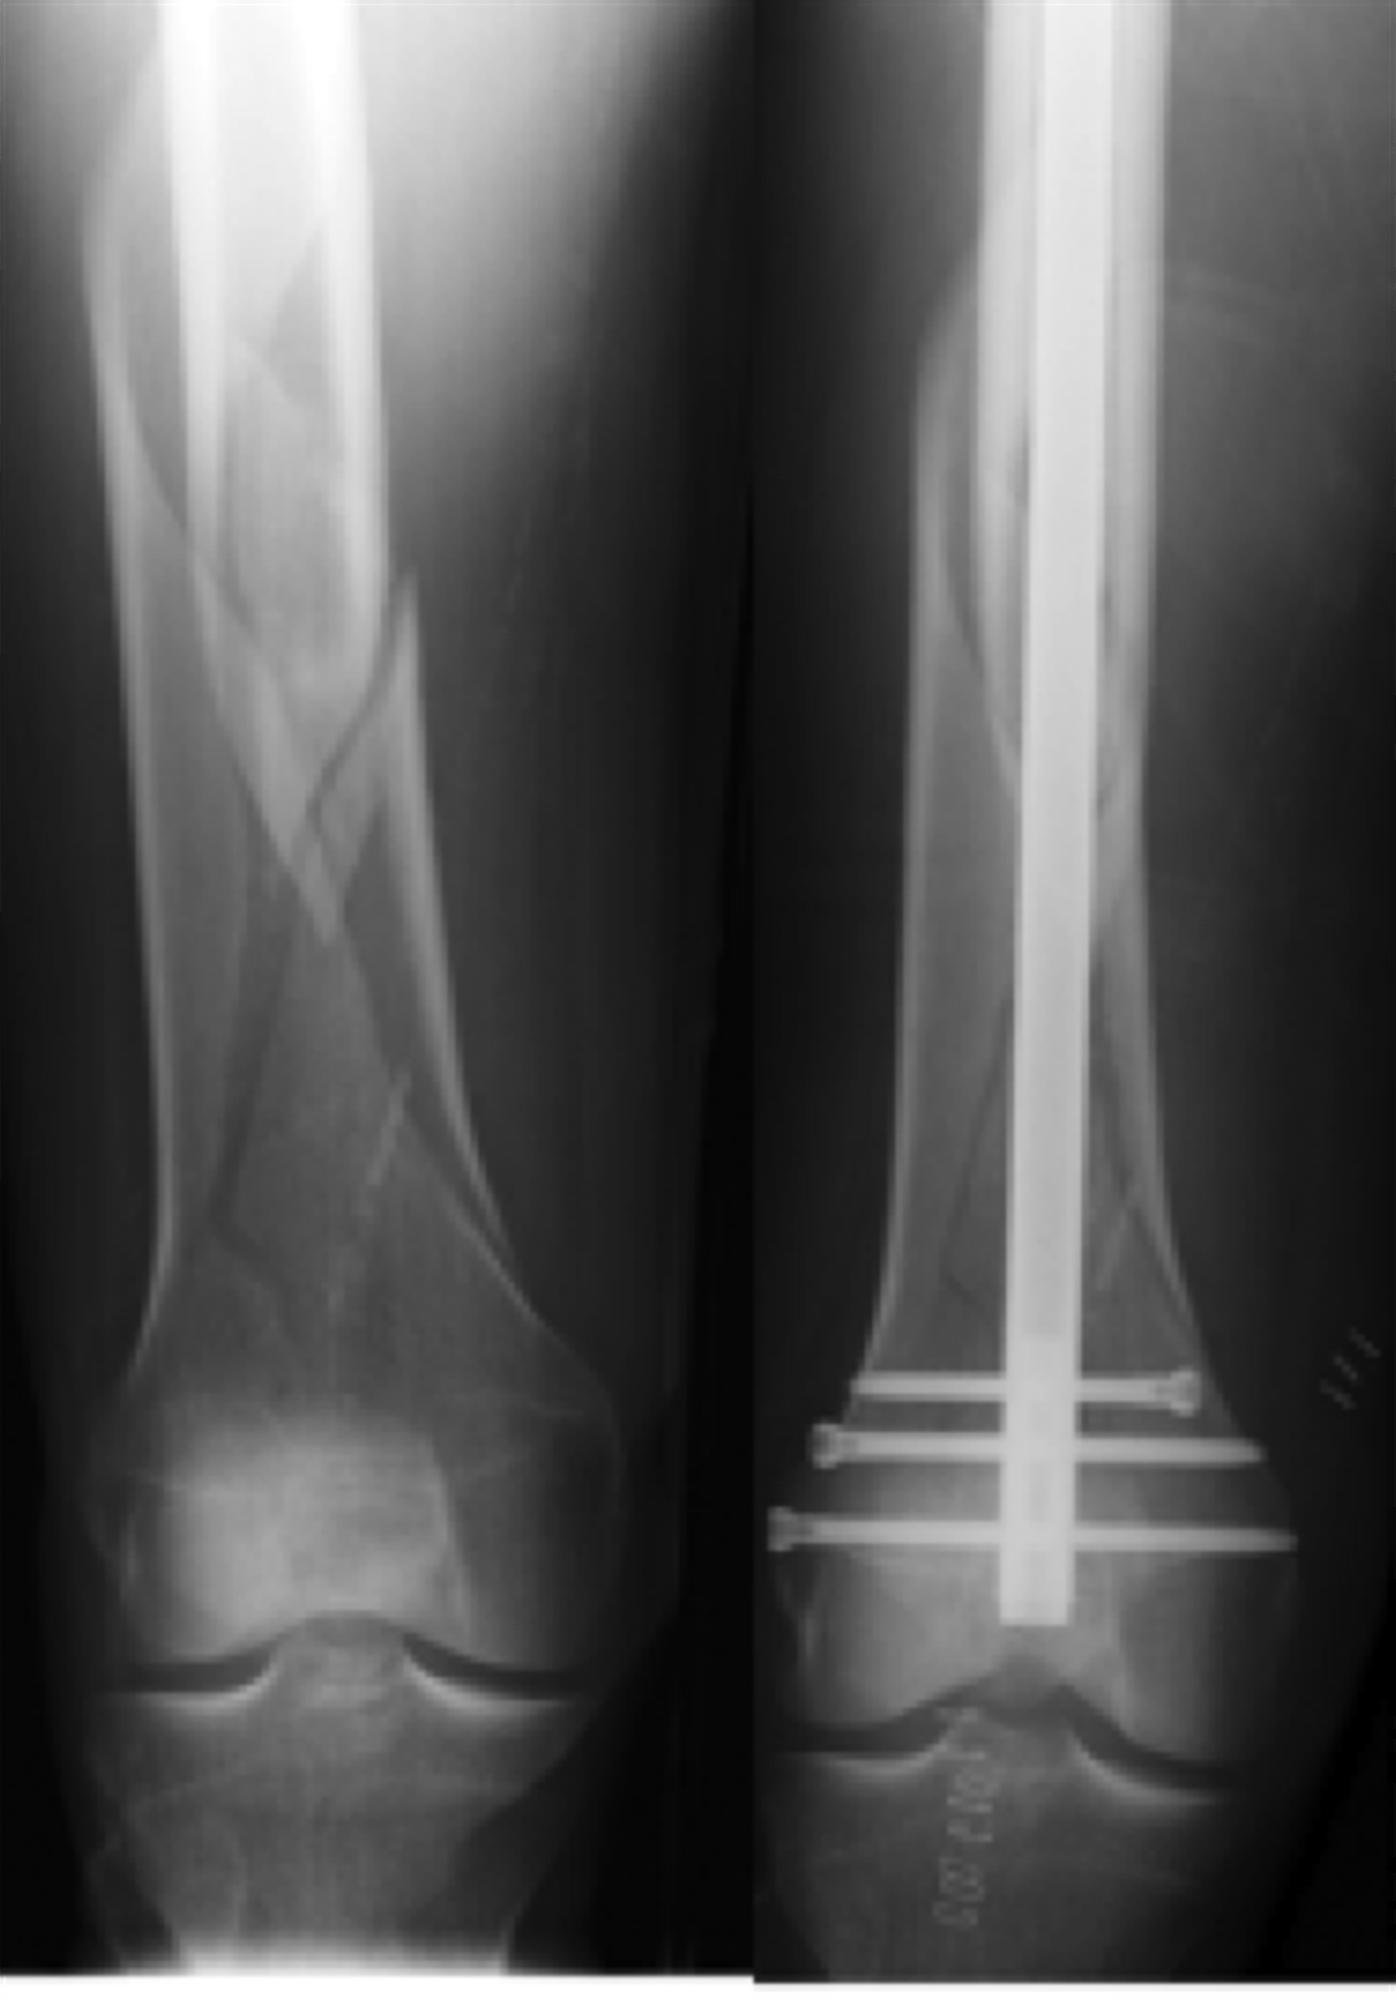

Femoral Shaft Fractures